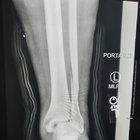

2023.05.28 07:24 MadamAndroid It’s been 2 years

It’s been 2 years

2 years ago today my husband fractured his ankle. It took 3 surgeries for him to stop asking for amputation. Posted with permission.

submitted by MadamAndroid to Radiology [link] [comments]